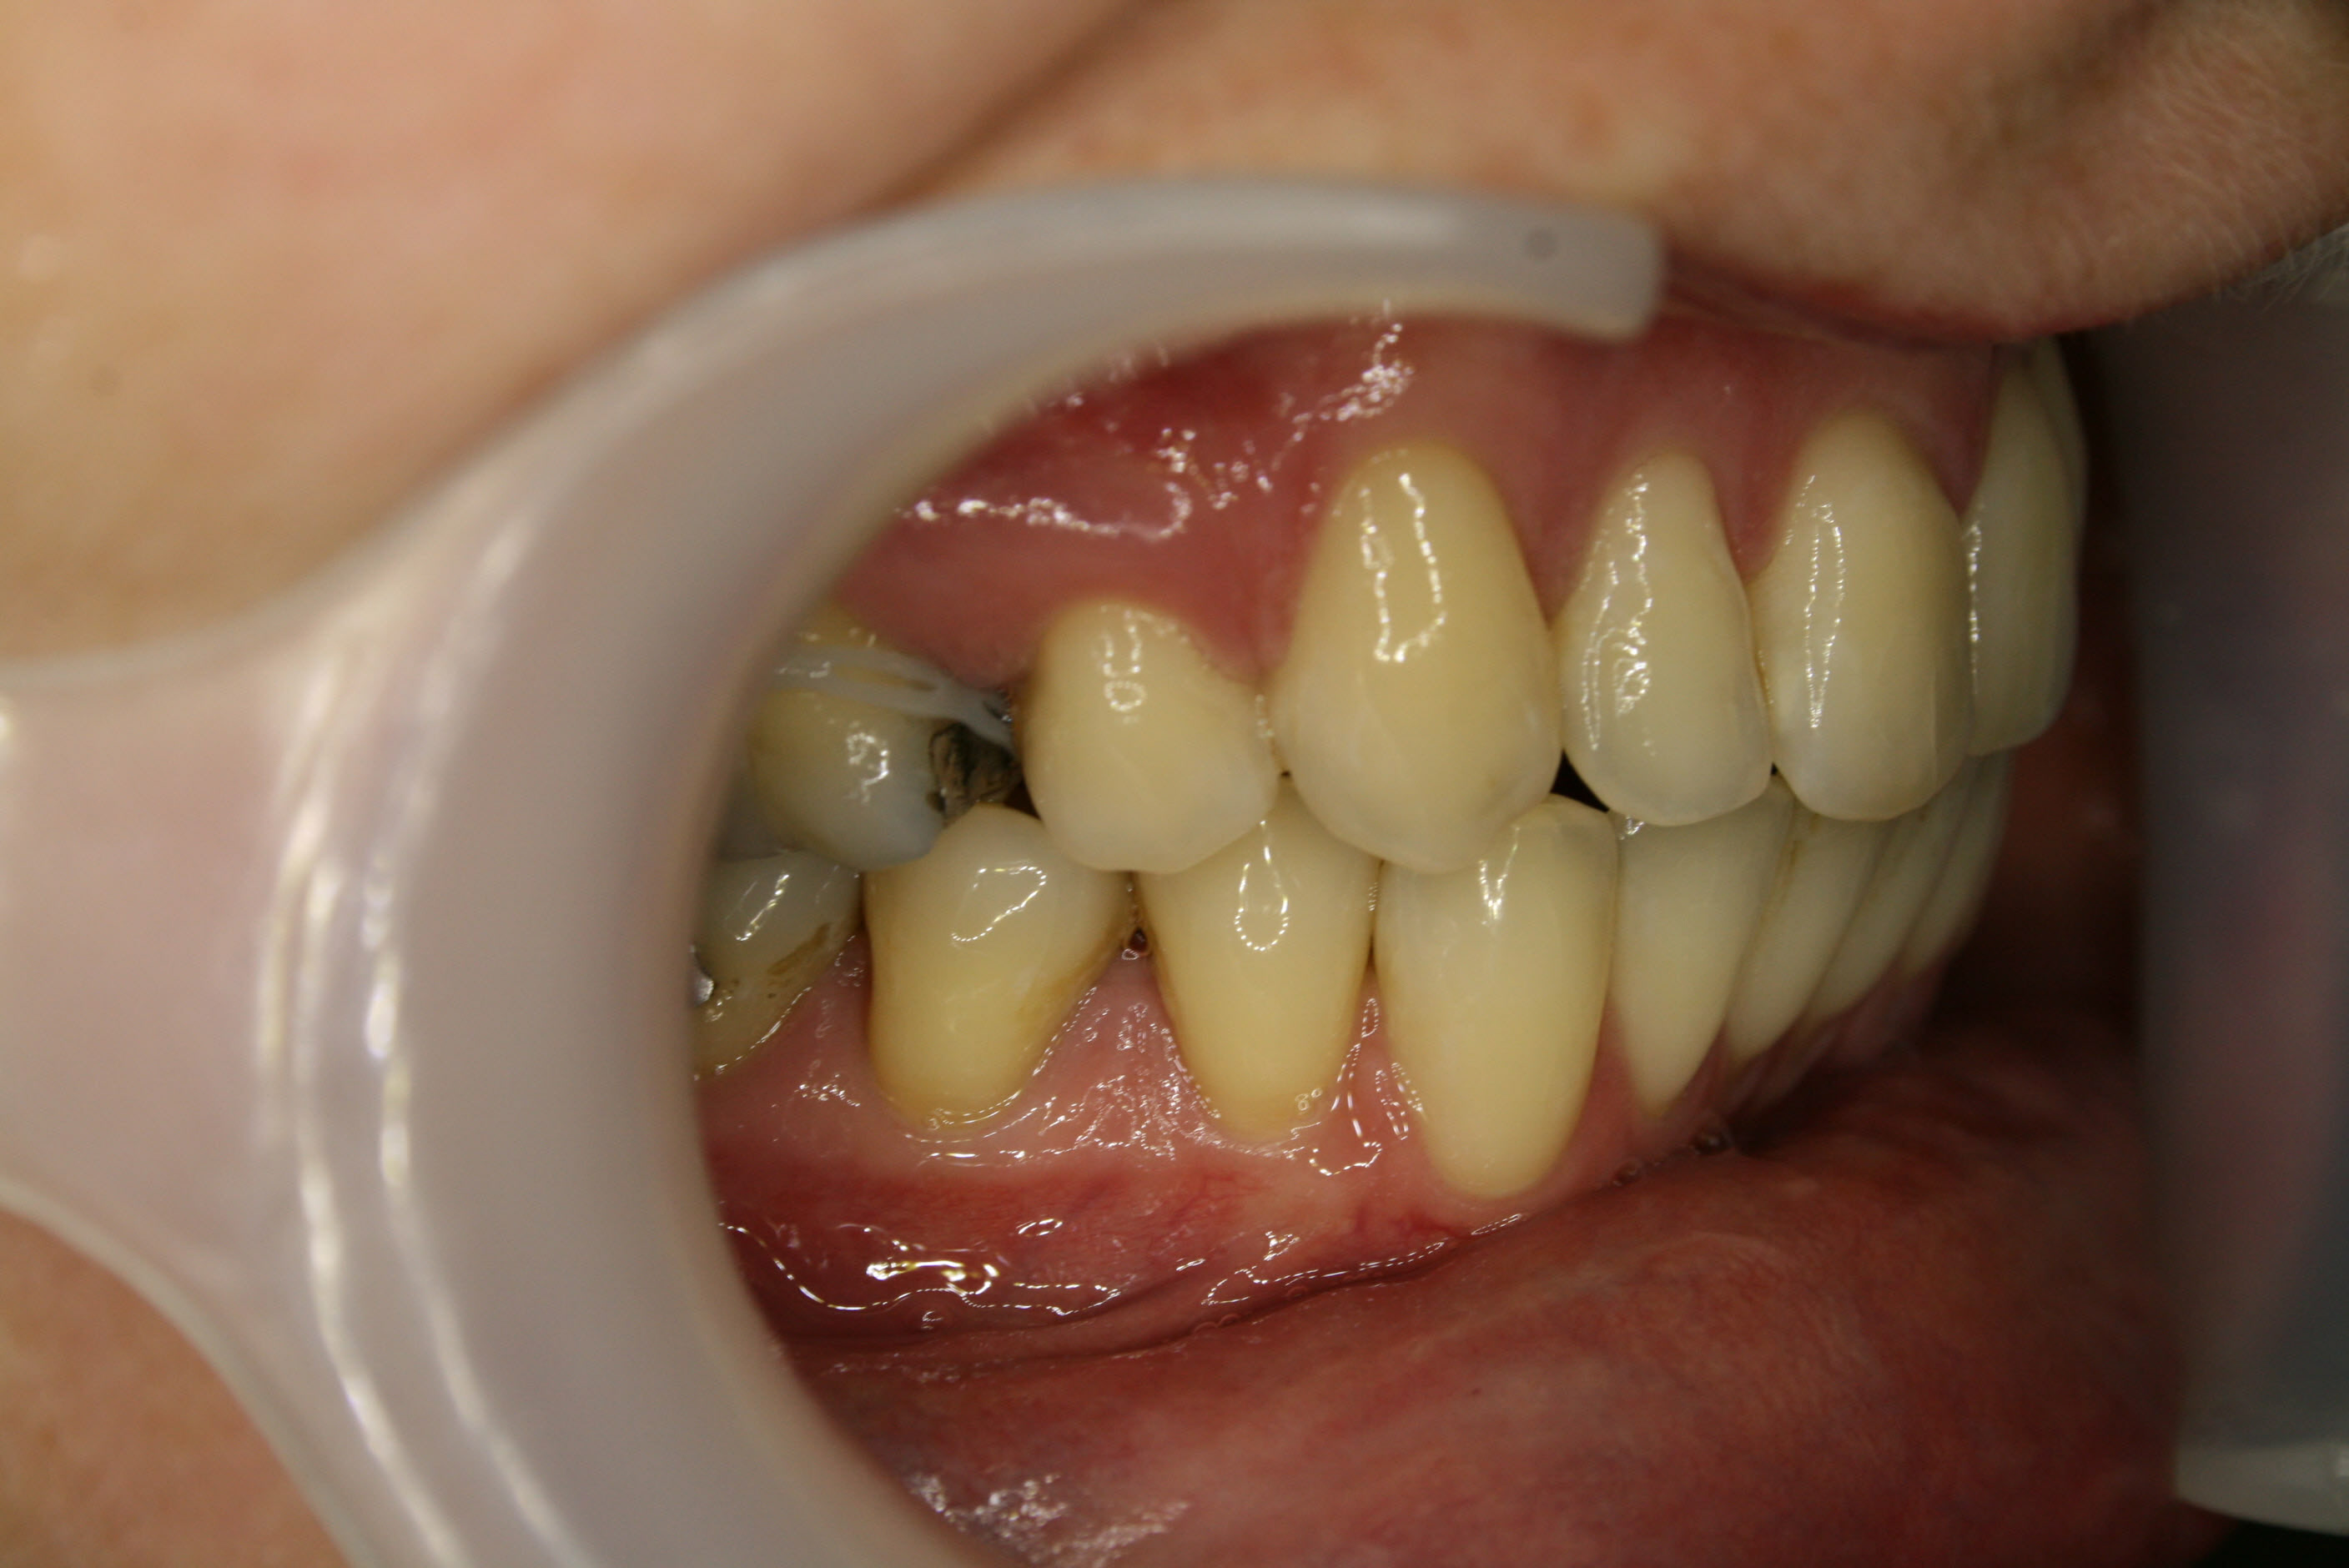

Lückenschluß in der Seitenansicht; hier ist gut zu erkennen, daß es gelungen war, den Lückenschluß von vorne her und achsengerecht auszuführen.